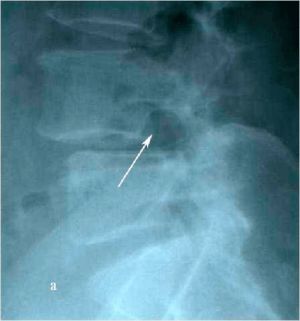

При МРТ и рентгенографии поясничного отдела позвоночника выявляется спондилолизный антеролистез L4 позвонка со стенозированием позвоночного канала на указанном уровне, грыжа мп диска L4-L5 слева. (Рис.7а,б. Рис.8а,б)

Рис. 8а. Рентгенограмма поясничного отдела позвоночника в боковой (а) и прямой (b) проекциях до операции. Стрелкой показано смещение тела L4 позвонка кпереди. Рис. 8b. Рентгенограмма поясничного отдела позвоночника в боковой (а) и прямой (b) проекциях до операции. Стрелкой показано смещение тела L4 позвонка кпереди.

Рис. 8а,b. Рентгенограмма поясничного отдела позвоночника в боковой (а) и прямой (b) проекциях до операции. Стрелкой показано смещение тела L4 позвонка кпереди.